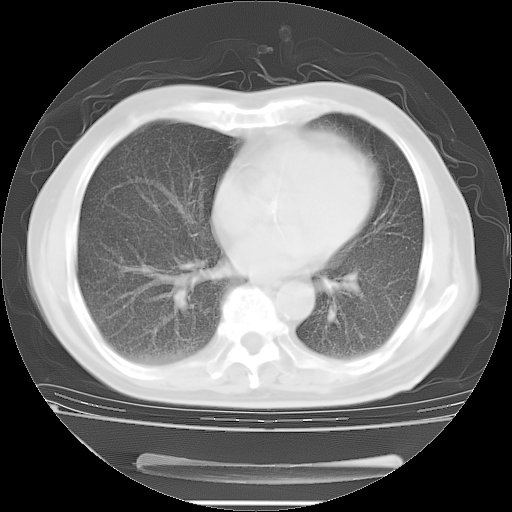

今天复查肺部CT,发现双肺广泛磨玻璃样改变。所以我把3月19日和5月9日相隔50天的肺部CT上传。请大家会诊。

5月9日肺部CT(在4月27日齐鲁医院肺部CT描述部分肺组织磨玻璃样改变,12天后肺组织广泛磨玻璃样改变)

2009年5月9日肺部CT

大致读了系列胸部CT:纵隔窗无明显异常,肺窗:从4、27至今:主要是双肺中下野外带可见毛玻璃样改变,目前处于急性肺泡炎阶段,至于原因考虑1、结替组织或胶原血管性疾病所致?2、恶性疾病如恶组在肺部所致的表现或细支气管肺泡癌?3、药物或其它原因如肺蛋白沉着症所致肺泡炎目前不太可能?总之,明天就去请我院的呼吸科、感染科、血液科和临免专家会诊哈。